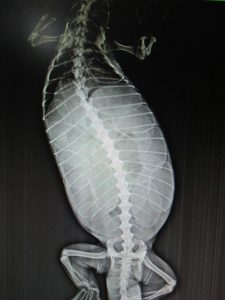

large monitor lizard on a towelAfter correcting the dehydration and taking X-rays, we discovered the huge abdominal bulge was due to her being egg bound. She was extremely listless and was in chronic pain with her eyes shut for almost two weeks. As days went by, painkillers daily, calcium intake, and other supportive treatment kept being given. The hope was that the lizard would slowly gain the strength to get the eggs out.